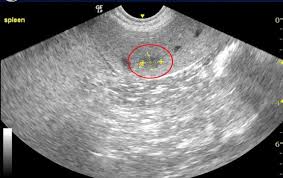

Symptoms of canine spleen cancer dogs with hemangiosarcoma in the spleen may not show any symptoms at the early stage. It's important to rush your dog to a veterinarian if any of these signs occur. While it is less frequent compared to liver cancer, for example, spleen cancer can be seen in a number of cases. Most dogs presenting with this cancer are brought to their veterinarian by their owners on an emergent basis due to a range of nonspecific clinical signs such as: Sometimes, it isn't found until one of the tumors ruptures and causes internal bleeding. Symptoms are generally related to the organs involved; How common is cancer in dogs, and what are some of the common. Only after an autopsy is the cancerous tumor on the spleen discovered. What are the symptoms of spleen tumors in cats and dogs? When to euthanize a dog with hemangiosarcoma Unfortunately, one of the most common initial signs of hemangiosarcoma involves sudden collapse due to massive internal bleeding, usually from a ruptured spleen. Chronic weakness, lack of appetite, weight loss), abdominal swelling, collapse and acute death if the tumor ruptures and bleeds internally. What are the symptoms of spleen cancer in dogs?

Studies find that 1 out of 4 dogs with cancer of the spleen also have tumors on their heart. When to euthanize a dog with hemangiosarcoma Due to its insidious nature, a ruptured spleen caused by a malignant cancer in dogs, is often nicknamed as the silent killer. veterinarian dr. Tumor is found only in the spleen. The spleen is a very important organ in the body and it plays important roles in rbc regulation and the immune system of the pet. What are the symptoms of spleen tumors in cats and dogs? Since dogs usually show only mild warning signs, cases of hemangiosarcoma may not be detected until the cancer has reached an advanced stage. — lump in the abdominal area Often, a tumor will rupture causing the spleen to bleed and resulting in an internal hemorrhage. If a dog has splenic hemangiosarcoma, it means the cancerous blood vessels are located in the tissue of your dog's spleen. Some of the symptoms that pet parents can be on the lookout for: It is a cancer made up of the cells that line blood vessels, and therefore can be found in any part of the body. Symptoms of dog spleen cancer are nonspecific;

Cancer is the leading cause of death in dogs over the age of 10. The cancer appears at a slightly elevated rate in male dogs over female dogs, and is more commonly found in the boxer, english setter, german shepherd, golden retriever, great dane and pointer breeds. That is, a tumor of the spleen will result in impaired spleen function, and a tumor of the liver will result in impaired liver function. Decreased appetite, weight loss, lethargy, increased/labored breathing, swelling of the abdomen, and acute collapse/weakness. But half of all cancers are curable if caught early, experts say. How is the diagnosis of spleen tumors made in cats and dogs? Which means that diagnosis depends upon the location, type and status of the cancer. A mass in the spleen is generally not detected until it becomes cancerous and begins to produce symptoms. Sometimes, clinical signs occur suddenly as a result of the rupture of the tumor in the spleen and significant internal bleeding. Visible bleeding is the most common symptom associated with spleen tumor. Hemangiosarcoma attacks the spleen, liver, heart, and skin. The average age of occurrence is 8 to 10 years, but it has been seen in dogs younger than one year of age. Common symptoms in affected dogs include abdominal pain, subnormal temperature, anorexia (appetite loss) and acute weakness.